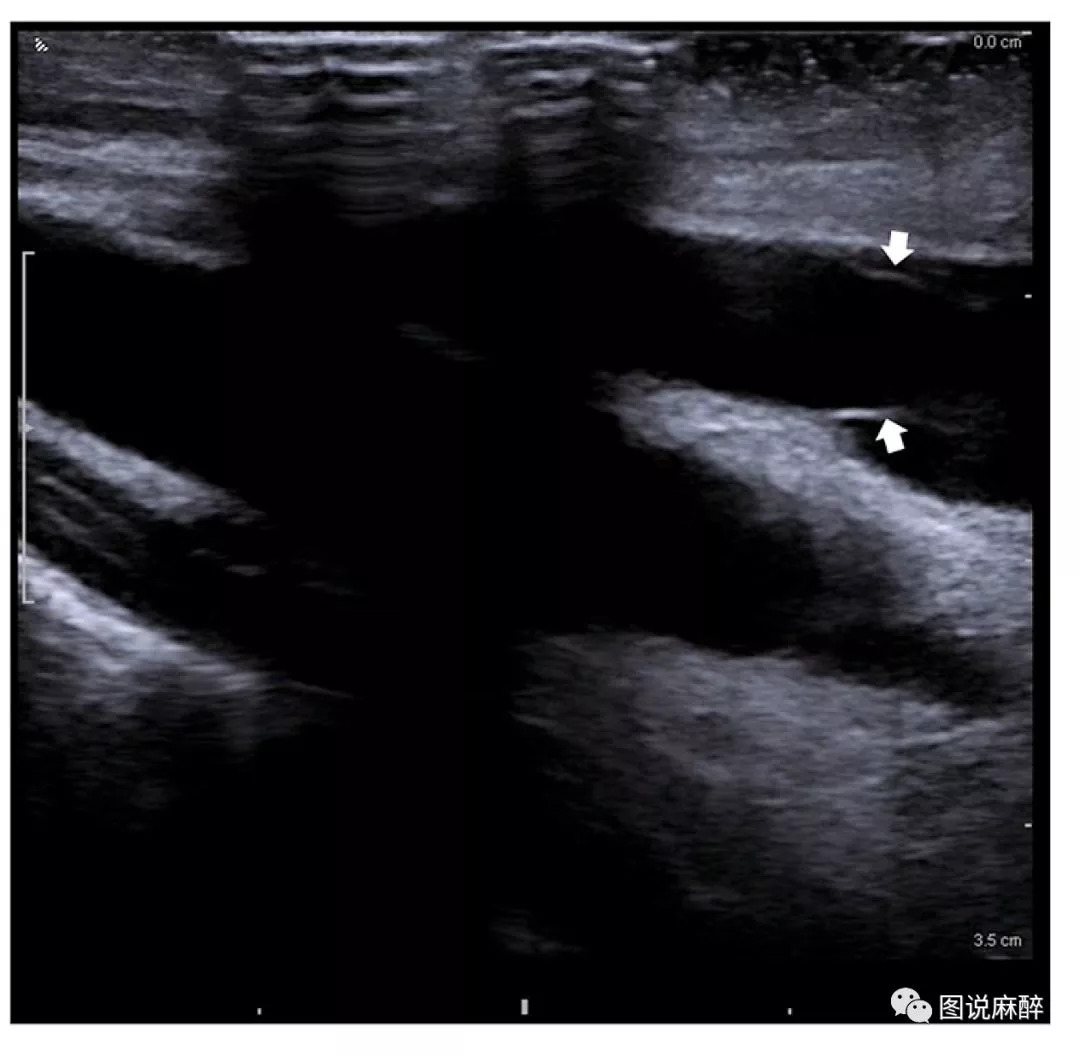

颈内静脉长轴观,可见瓣状物为颈内静脉瓣。

声像图上颈静脉瓣呈带样强回声,根部附着于静脉壁上,瓣膜游离缘指向心脏方向。